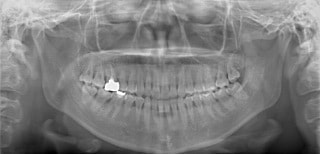

検査時パノラマレントゲン

全体の歯根のパラレリング(平行性)は悪い状態ではありません。顎関節の変形などはありません。鼻閉もありません。

成人の反対咬合なので、少し顎関節にダメージはありますが、重症ではありません。CO(中心咬合位)の位置には問題があります。CO-CRのズレが存在しますので、顎関節には負担がかかっています。